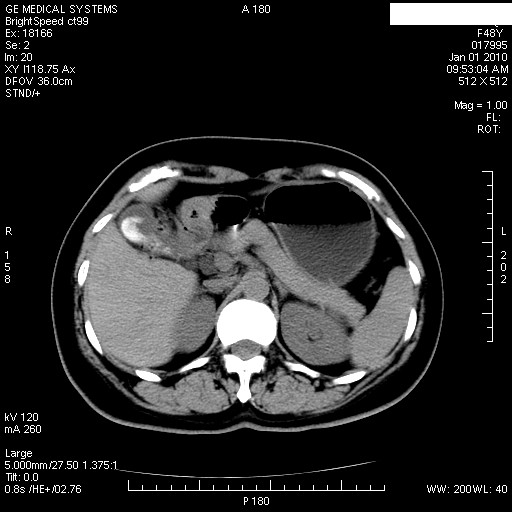

经过抗炎解痉镇痛治疗一周后复查ct如下:

1.图像看上去不是同一人(前组图像十二指肠未见明显异常,后组图像可见十二指肠占位)

2.后组图象印像

a.十二指肠球部前壁占位

b.坏蛆性胆囊炎,胆囊-结肠瘘(瘘口微小且时间较短,结肠内容返流入胆囊,形成胆囊壁钙化,胆囊内钙盐等沉积)

c.胆管炎,肝外胆管轻度扩张